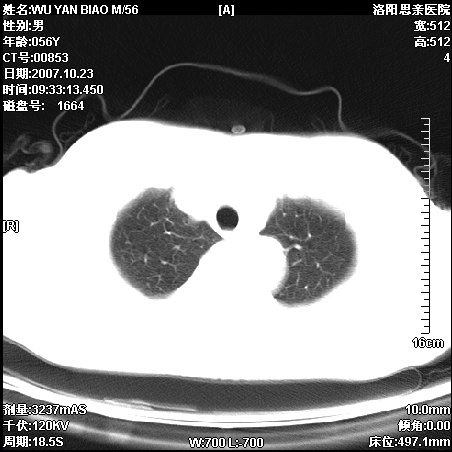

标题: CT10160:M56Y,体检发现,病人无不适,病人随访中 [打印本页]

标题: CT10160:M56Y,体检发现,病人无不适,病人随访中

后上纵隔占位,与肺交界清,宽基底附着脊柱,密度均匀,局部骨质无明确改变.

考虑;神经源性肿瘤,---起源交感n链?,不除外肠源性囊肿.

1、病灶在后纵隔脊柱旁沟内,此处是神经原性肿瘤的好发部位

2、病灶边缘光滑整齐,更说明病灶来于纵隔,由于有胸膜的包裹所以才导致这么光滑的边缘

3、病灶内的密度均匀